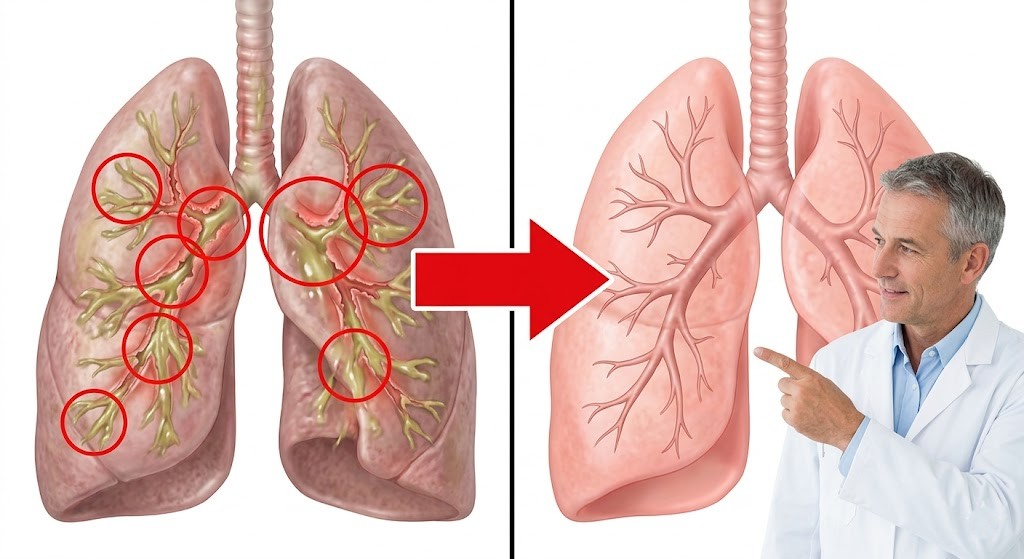

Was sie fanden: In den Atemwegen jedes einzelnen Patienten befand sich eine dichte Schleimschicht ganz unten – unter dem frischen Schleim, unter der Reichweite jeder Behandlung.

Die Schicht war seit Monaten dort gewesen. Manchmal über ein Jahr.

Die Flimmerhärchen – diese winzigen Härchen, die den Schleim hinaustransportieren – waren vollständig darunter begraben. Funktionslos.

Die Forscher testeten Standardbehandlungen an dieser untersten Schicht.

Nichts funktionierte. Nicht ACC. Nicht Kochsalz-Inhalatoren. Nicht NAC. Kein Schleimlöser und kein Nahrungsergänzungsmittel.

Die molekulare Struktur war anders. Dichter.

Oberflächenbehandlungen konnten sie nicht auflösen.

„Das hier ist das, was Sie jeden Morgen abhusten. Frischer Schleim. ACC löst diesen. Ihr Inhalator hilft dabei."

„Aber darunter gibt es eine weitere Schicht. Alter Schleim. Monate alt, vielleicht Jahre. Ihre Flimmerhärchen sind darunter begraben."

Er zeigte erneut auf die unterste Schicht.

„Das ist der Unterschied. Alles, was Sie versucht haben, wirkt auf das, was Sie abhusten können. Aber diese Schicht? Sie ist zu tief. Zu verhärtet. Oberflächenbehandlungen können sie nicht berühren."